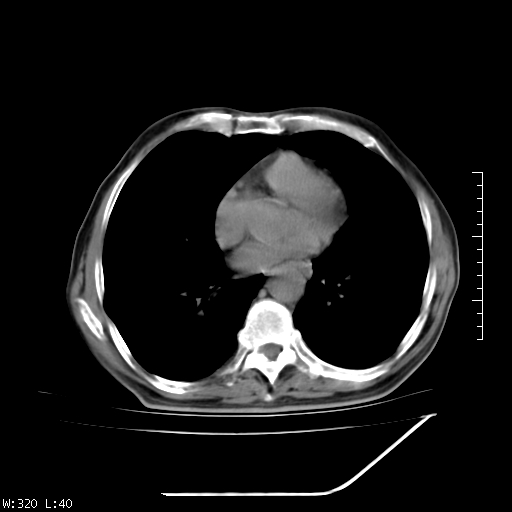

标题: CT23994:男、72、咳嗽、气短两月余,近来消瘦。 [打印本页]

标题: CT23994:男、72、咳嗽、气短两月余,近来消瘦。

右上肺实变,与胸膜关系密切,右肺容积缩小,隆突下淋巴结增大,考虑1 肺结核 2 肺癌

右上肺大片状密度增高影,与胸膜关系密切,内见低密度透亮影,胸膜下可见三角形不张影,左下肺沿支气管走形结节影,纵膈内淋巴结显示。考虑结核并疤痕性不张可能性大,建议穿刺活检,排除肺泡癌。